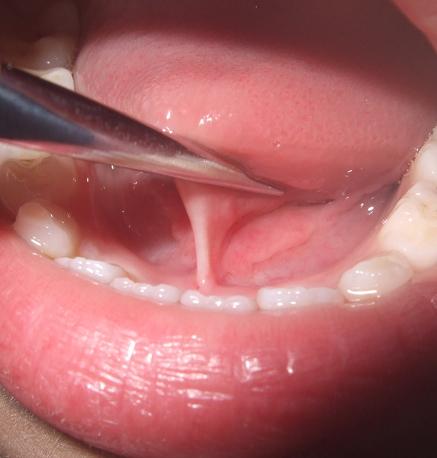

舌头下面正中的“筋”就是舌系带

张大嘴上抬舌头,可以看到舌头下面正中连着的一根“筋”,这便是舌系带。

我们所谓的舌系带过短指的是舌系带与舌腹以及口底的附丽点过于靠前,使得舌体的上抬、前伸以及左右摆动活动受到限制。

- 舌系带过短导致舌头不能正常伸出口外,勉强伸舌时,舌尖会出现由于舌系带牵拉导致的凹陷;

- 将嘴巴张到最大时,上抬舌头,舌尖不能舔到上门牙或者腭部。